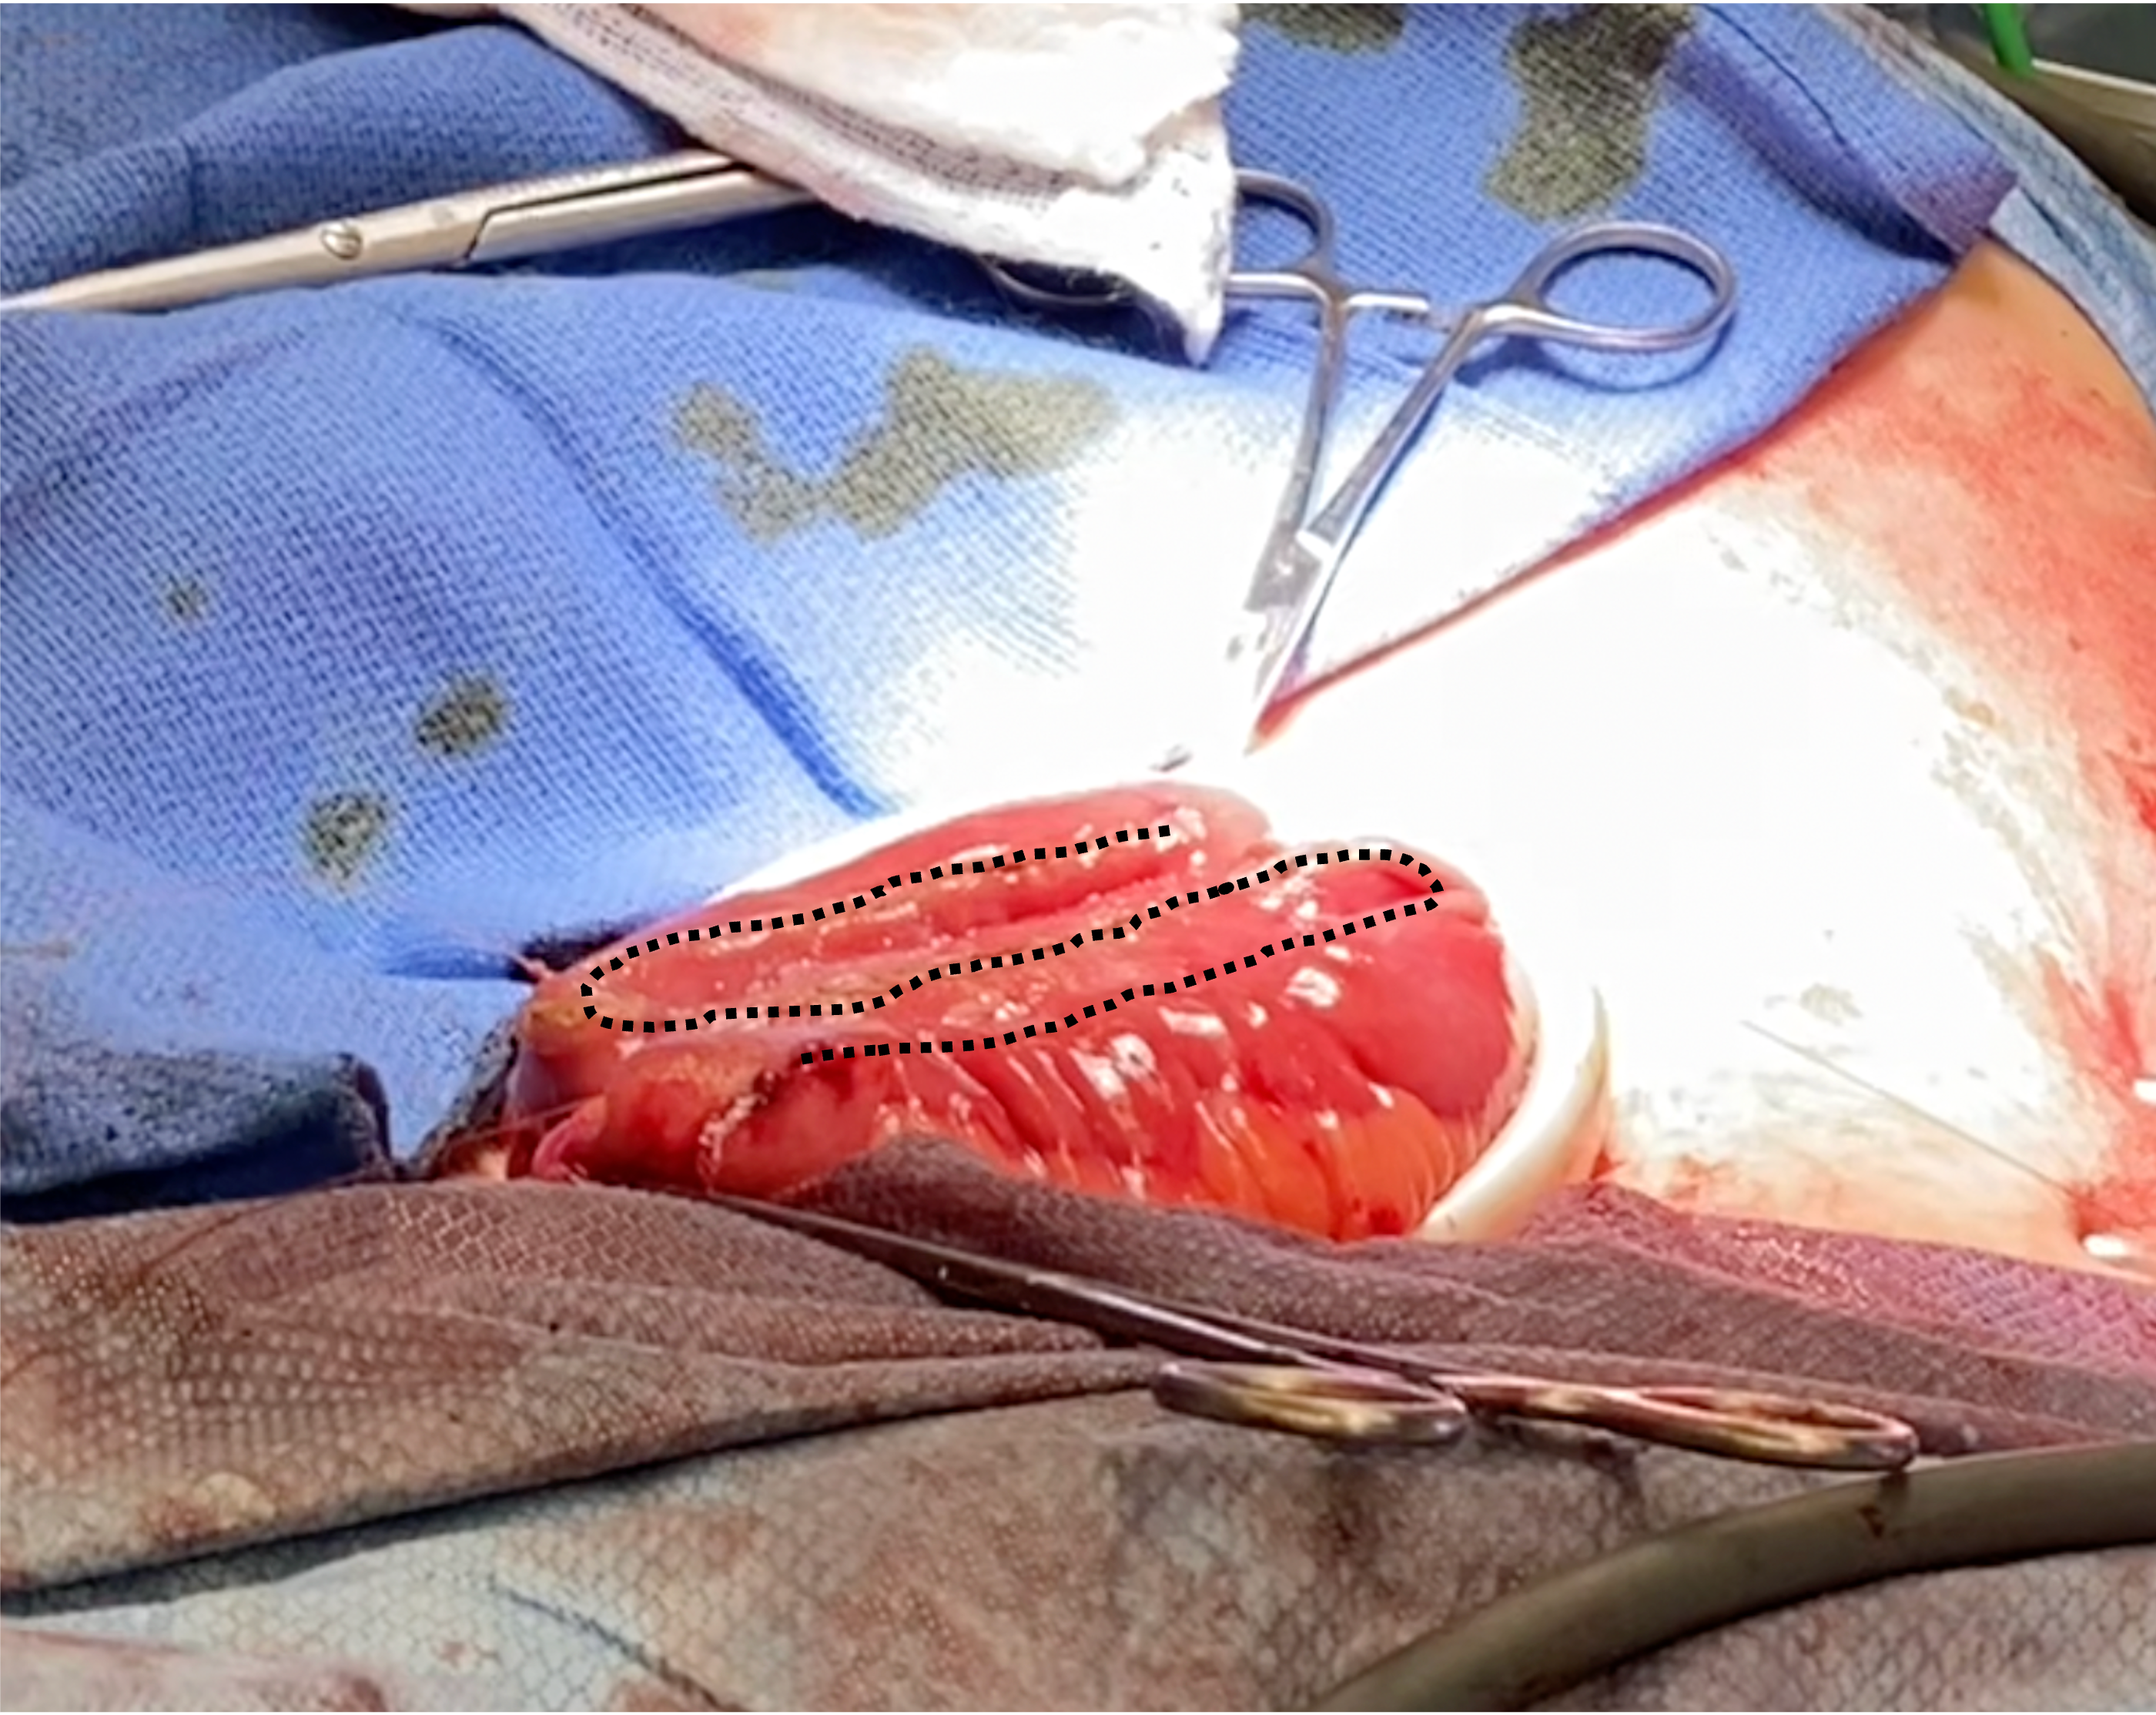

S-pouch incision

Planning the S-pouch enterotomy, ensuring the incision on the outer limbs is close to the inner limb to allow for the largest possible pouch size.

Planning the S-pouch enterotomy, ensuring the incision on the outer limbs is close to the inner limb to allow for the largest possible pouch size.